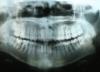

перекрестный прикус, мезиальная окклюзия. щелкает сустав при зевании. ничего пока не болит. внешняя ассиметрия лица усугубляется со временем. на КТ нашли начальную стадию деформирующего артроза вчс справа. наклон зубов, как мне сказали, критический.

мнения разделились. одни говорят, это операция на обеих челюстях + 3 года как минимум в бреккетах. другие хотят выдрать чертверки и передвинуть зубки, но челюсть при этом останется кривой. третьи говорят, или операция или вообще ничего не трогайте, природа компенсирует. на этом я пока и остановилась. но фотографии мне мои не нравятся.